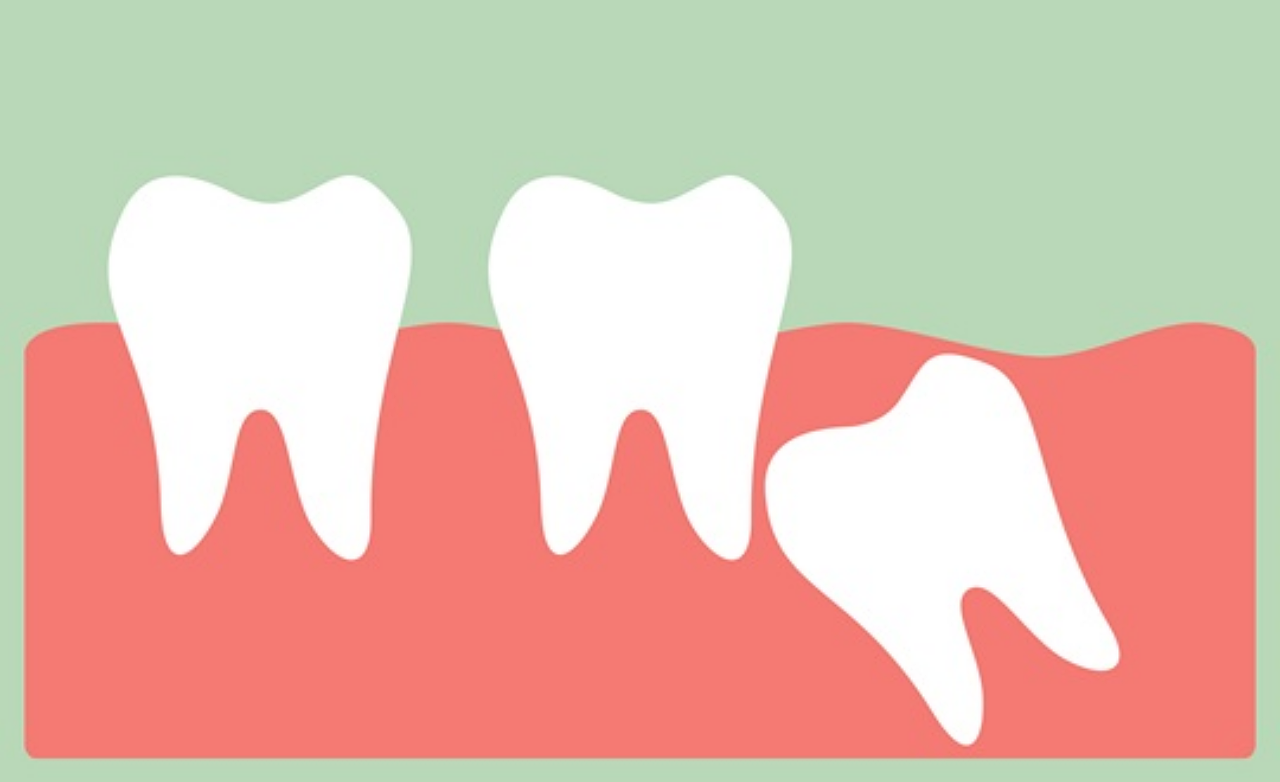

사랑니 발치하지 않고 방치한다면? 사랑니부었을 때 발치를 하지 않고 그대로 방치하면 다양한 문제들이 생기게 됩니다. 구경염증, 충치, 합병증등이 생기게 되는데 염증과 충치는 당연히 생기게 되면 심각한 사랑니 통증으로 잠을 잘 수도 없게 될 수 있습니다. 또 사랑니가 올바르게 나지 않은 상태라면 치아가 고르지 못하게 생기게 되어서 교정을 받아야 될 수도 있습니다. 또 사랑니 통증이 오래가고 있는데 발치 않할 때 합병증으로는 함치성낭종, 치관주위염 등과 같은 문제들이 생기게 될 수 있다고 합니다.